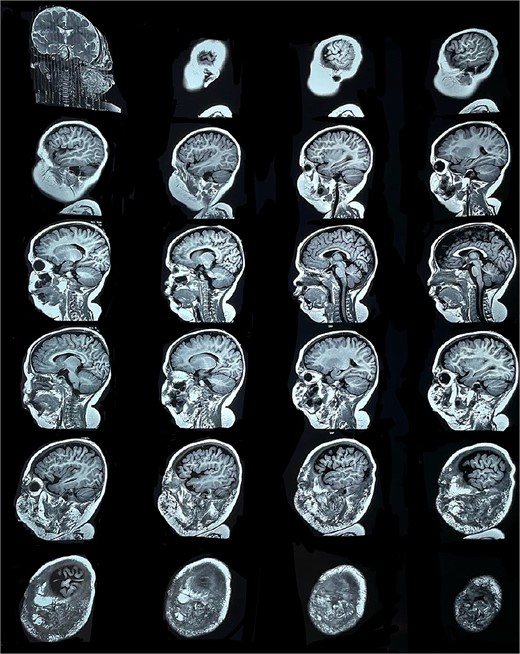

Six months later, the patient developed fever and severe edema that prevented the opening of the left eye, resulting in decreased overall tolerance. Laboratory results showed leukocytosis, severe thrombocytopenia (platelet count of 6000), and a positive C-reactive protein test. Physical examination revealed an irritable and lethargic patient with a 15 × 20 cm red mass with irregular borders (Fig. 1). An angioresonance was performed, revealing a hemangioma on the left hemiface that infiltrates muscle planes, the left parotid gland, and the auricular pavilion, ~10.7 × 6.6 × 13 cm in size, with possible vascularization from branches of the external carotid artery (Figs 2 and 3), leading to the diagnosis of KMP.

Angioresonance with evidence of a hemangioma on left hemiphase (cross-sectional).